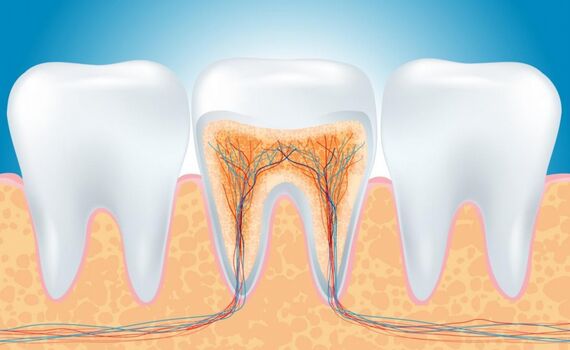

Если кариозный процесс зашел так далеко, что затронул уже сосудисто-нервый пучок зуба (так называемый «нерв»), необходимо эндодонтическое лечение: удаление пресловутого «нерва» и последующее пломбирование корневых каналов. И здесь решающим фактором, определяющим успех лечения, является качественное пломбирование корневых каналов.

Сейчас при определении длины каналов врач оперирует величинами порядка 0,5 мм в ту или иную сторону. Только такая высокая точность манипуляций может дать врачу и пациенту уверенность в том, что депульпированный (лишенный «нерва») зуб долгие годы будет служить верой и правдой, не доставляя пациенту (а значит и врачу) страданий и хлопот. А с учётом того, что современные технологии позволяют многократно (практически неограниченное количество раз) заменять отслужившие своё старые и изношенные протезы и пломбы, становится понятна важность хорошего, прочного «фундамента», коим и является грамотно запломбированный корневой канал.